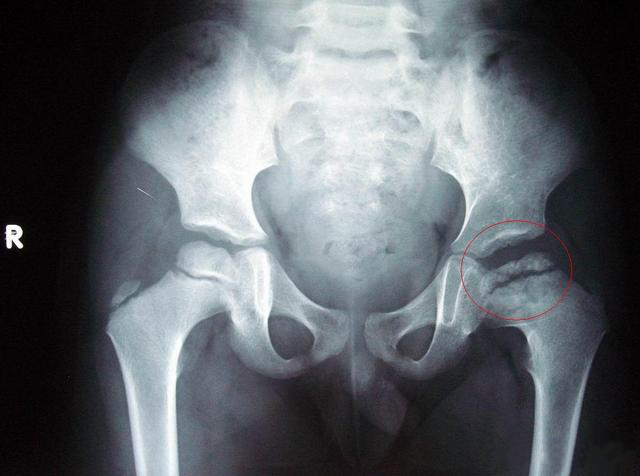

发育性髋关节发育不良

髋部和骨盆骨x线

后一个月,①术前左侧异常位置,此次手术将右侧股骨头下移至②正常位置

正常的左,右两处髋关节